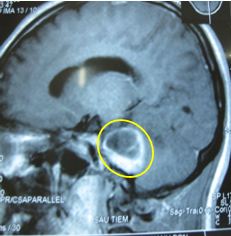

Trường hợp 2: Bệnh nhân nam, 56 tuổi. Được chẩn đoán là u dây thần kinh số VIII bên trái có các triệu chứng ban đầu: đau đầu, nôn, tê nửa mặt trái. Trên hình ảnh MRI sọ não trước và sau 1 năm, sau 2 năm xạ phẫu bằng dao gamma quay cho thấy khôi u đã mất. Các triệu chứng lâm sàng ban đầu đều hết, bệnh nhân không bị liệt mặt, sinh hoạt bình thường, chất lượng cuộc sống tốt.

Trước điều trị: u dây VIII bên       Sau điều trị 1 năm: u hoại tử               Sau 2 năm: u tiêu biến

trái kích thước 1,8cm

Hình 3: Hình ảnh MRI u dây VIII trước và sau xạ phẫu gamma quay